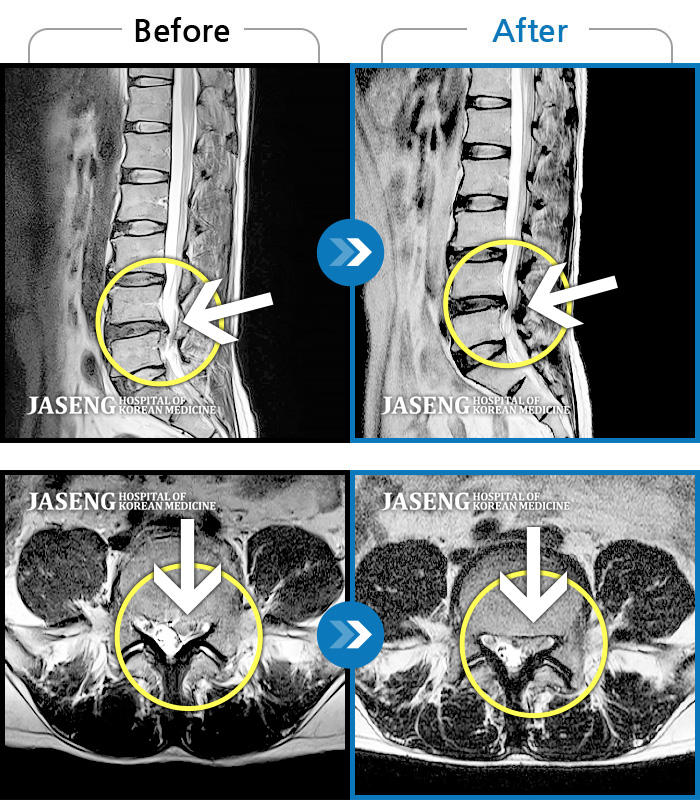

Before

After

환자에게 사전 동의를 받아 동일 조건에서 촬영되었습니다.

개인에 따라 치료 후 부작용이 발생할 수 있으니 의료진과 상담 후 치료를 진행하시기 바랍니다.

허리 양측부터 골반까지 통증, 우측 하지 내측으로 이어지는 당기는 통증 및 저린감

허리 양측부터 골반까지 통증, 우측 하지 후면으로 이어지는 당기는 통증